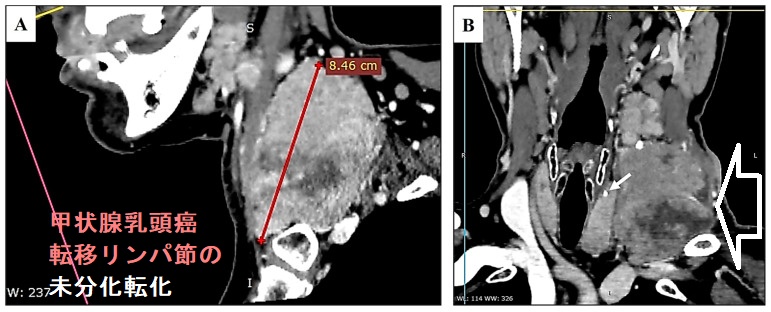

甲状腺乳頭癌の未分化転化は、0.8–2% の頻度で起こりえます。甲状腺乳頭癌の肺転移巣・遠隔転移巣や転移リンパ節が未分化転化する報告は多くあります[Ann Diagn Pathol. 2010 Feb;14(1):41-3.][J Surg Oncol. 1999 Jan;70(1):45-8. ]。